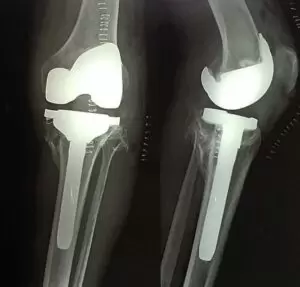

Dr Chethan has performed successfully Total Knee Replacement using Stryker Triathlon System

We performed a Total knee replacement (TKR) on him using the Stryker Triathlon system, which is a very advanced and versatile knee replacement device that provides a very high degree of knee bending.

TKR is not just about putting in an artificial joint made of metal and polyethylene, it involves getting the alignment perfect, balancing the ligaments and soft tissues, so that the knee joint moves freely, and ensuring that the tissues and wound heal without any further complications.